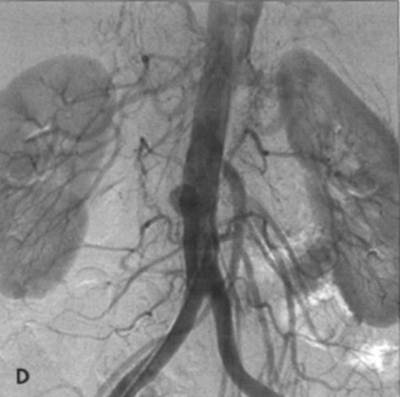

There is co-existing left common iliac occlusion. D - Angiographic appearance of re-implanted SMA into aorta, which has

a smal l saccular aneurysm at the site of occluded vein graft (aortoceliac bypass).